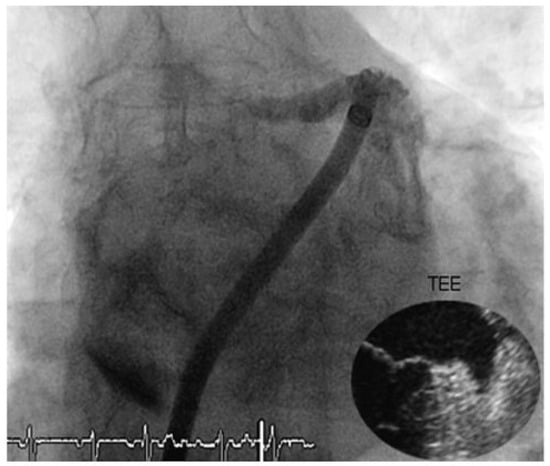

Muscular Ventricular Septal Defect After Mitral and Aortic Valve Replacement

by Augusto Aragão, Dorothea Vogel and Christoph Schmidt

Cardiovasc. Med. 2010, 13(5), 167; https://doi.org/10.4414/cvm.2010.01500 - 26 May 2010

We describe a case series of five patients who were referred to our cardiac rehabilitation department after mitral or aortic valve replacement, and whose transthoracic echocardiographic studies showed postoperative muscular septal defects. Full article